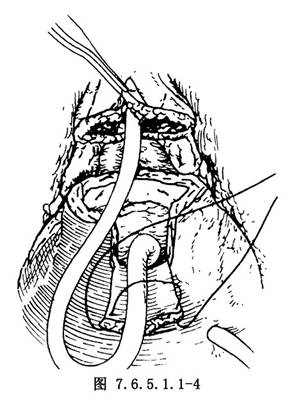

4.從兩遠側縫線分別向近側縫線平行切開膀胱前壁,上翻膀胱瓣。膀胱頂部戳口插入膀胱造口管。將膀胱瓣包繞已置入之氣囊導尿管,用3-0可吸收線全層縫合成管狀備用。同時,從前列腺前面楔形切下一塊組織,縫合切緣使開口縮小(圖7.6.5.1.1-4)。